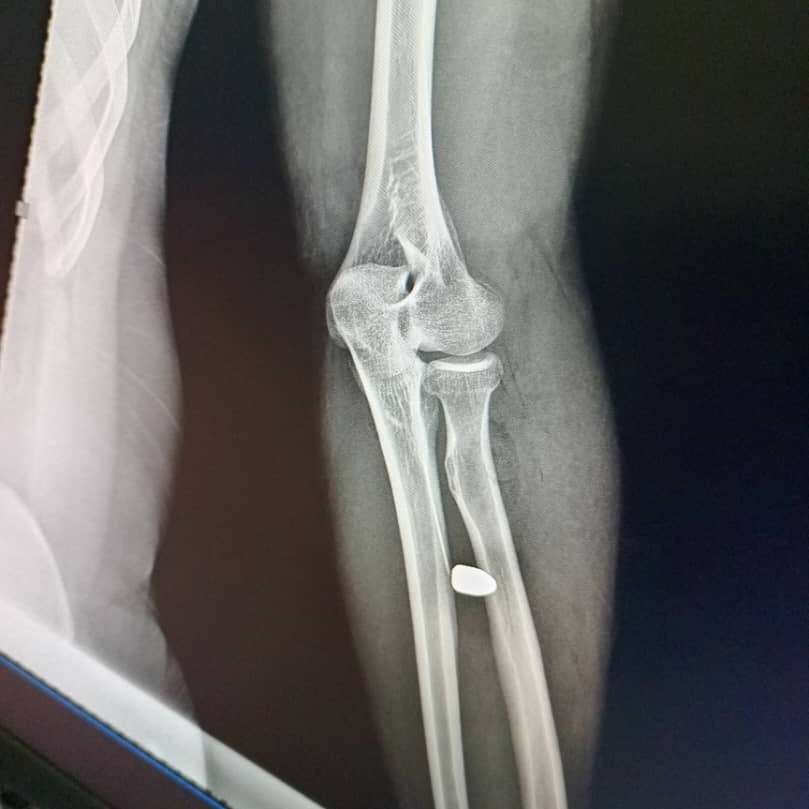

The x-ray image of a 25-year-old man who was struck in the arm by a stray bullet in the Rue de 30 Metres neighborhood, N’Djamena, on May 9, 2024 following the announcement of the provisional results of the Chad presidential elections. © 2024 Private